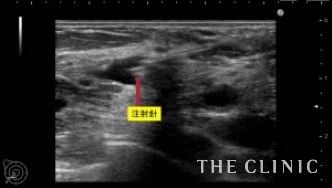

一つ一つヒアルロニダーゼ(ヒアルロン酸溶解剤)を注入して吸引していきます。